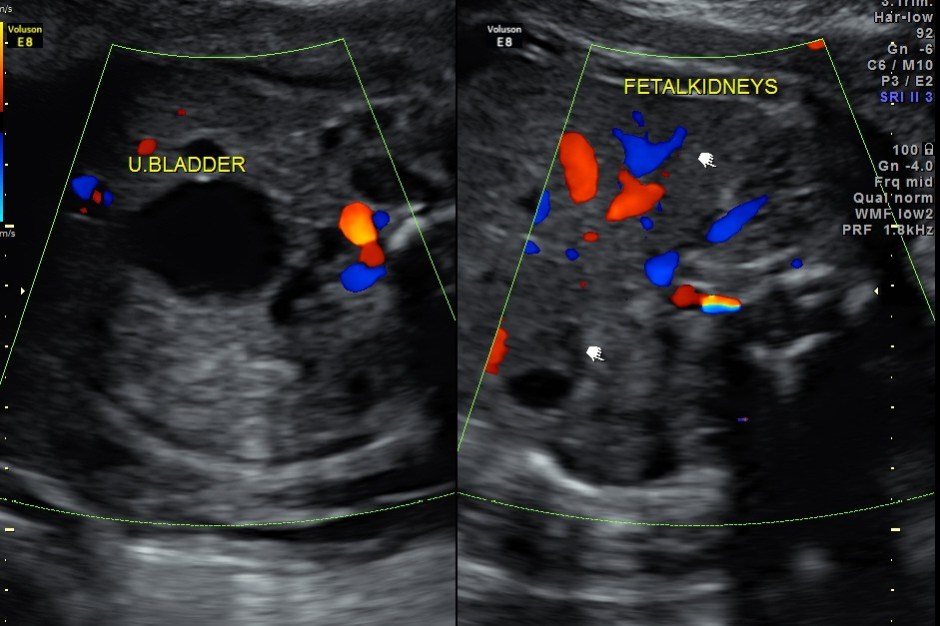

The following images show bilateral renal pelvi ectasis and bilateral dilated ureters with all the changes more in the left kidney .